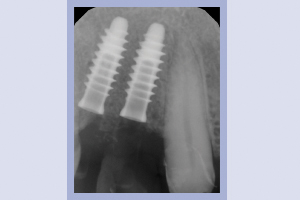

Il controllo clinico (Figg. 72-75) e radiografico 2D (Figg. 76-78) dopo 1 settimana conferma il perfetto stato di salute dei tessuti perimplantari e l’armoniosa integrazione della protesi provvisoria con la gengiva.

- Figg. 76-78 – Controllo radiografico a 1 settimana